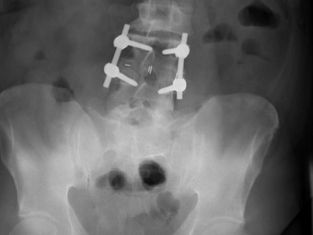

Is Chiropractic Care Recommended After Surgery?

Can a Chiropractor help after Spinal Surgery? Unfortunately, many patients who decide to see a Chiropractor for the first time do so after days- months- sometimes years- of suffering. Often, they’ve tried every medication, massage, stretch and specialist on the planet, many of them even having had surgery. As most people find, if your spine is subluxated, out of alignment, it is unlikely that there is a ‘quick fix’, and that’s why they finally end up on our doorstep. A freque